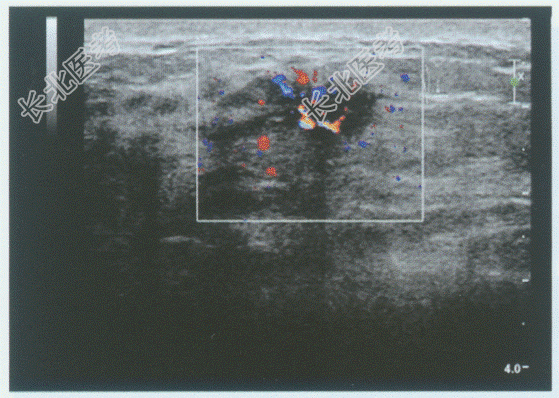

超声综合描述: 右乳外上象限可见2.0cm×1.5cm低回声区,形态欠规则, 边界不平呈锯齿状,内回声不均, 可见点状强回声,CDFI: 内可见较丰富点棒状动静脉血流信号,V

31.0cm/s。见下图及彩图。